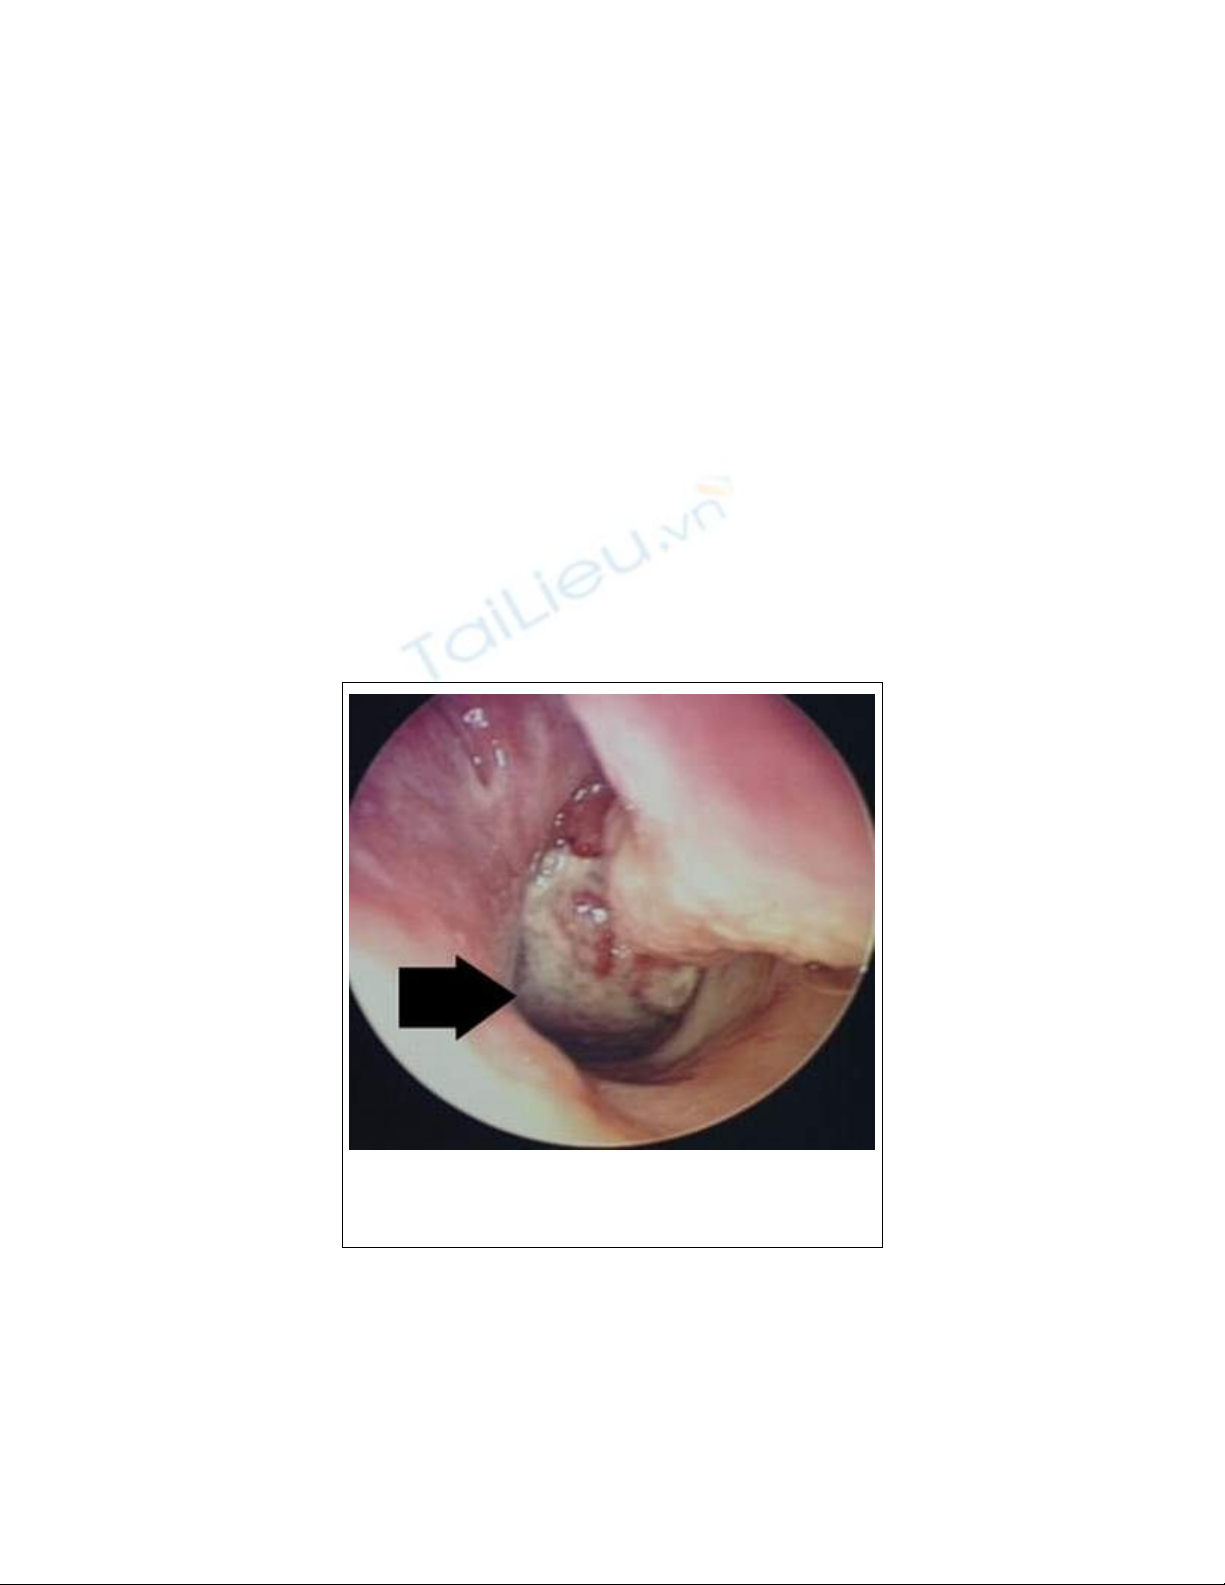

Khối u vòm mũi họng.

bao bọc toàn bộ khối u. Khám hốc mũi thấy một khối u màu hồng

nhạt, nằm bịt cửa mũi sau, khi phát triển lớn lấp đầy hốc mũi, khối

u đẩy dồn làm hẹp hốc mũi bên đối diện, nhưng không làm tổn

thương niêm mạc mũi. Khám họng và soi mũi sau thấy màn hầu

phồng lên, bị đẩy dồn về phía trước và phía dưới hoặc quá to thòi

xuống tận họng miệng. Nhức đầu kèm theo gặp trong khoảng 25%